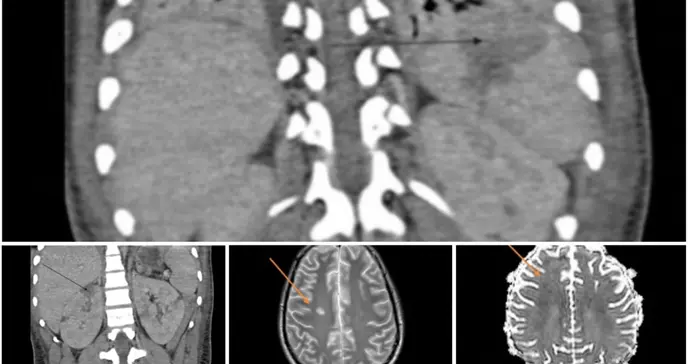

La tomografía computarizada abdominal demostró hallazgos inesperados y graves: distensión intestinal acompañada de infartos esplénicos y renales bilaterales.

La particularidad de este caso es por la gravedad de las complicaciones trombóticas, específicamente los infartos esplénicos y renales bilaterales, esta última una manifestación extremadamente rara que requirió terapia de reemplazo renal. Además, se documentó la presencia de anticuerpos antifosfolípidos de clase IgA, un hallazgo inusual cuya asociación con eventos trombóticos en el contexto de COVID-19/MIS-C aún no está completamente elucidada y merece mayor investigación.